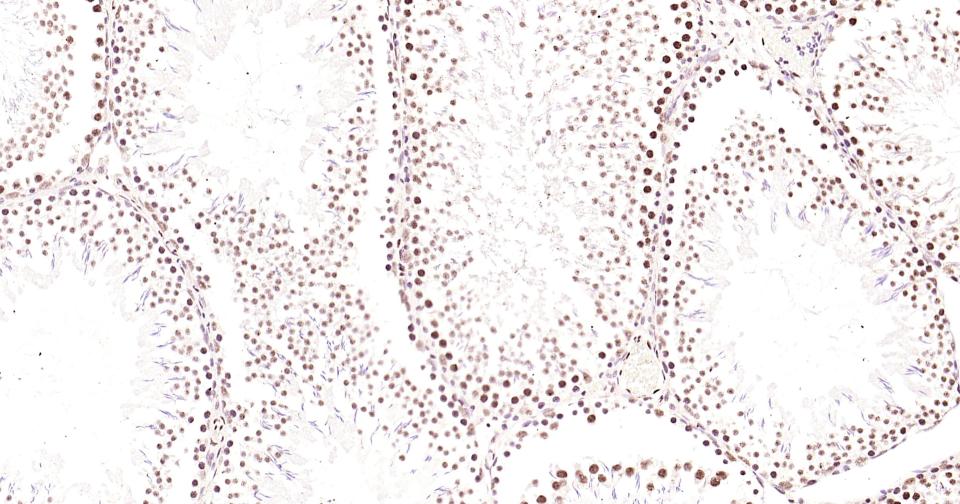

Paraformaldehyde-fixed, paraffin embedded Mouse Testicles; Antigen retrieval by boiling in sodium citrate buffer (pH6.0) for 15 min; Antibody incubation with Phospho-CREB-1 (Ser133) Monoclonal Antibody, Unconjugated(bsm-61105R) at 1:200 overnight at 4°C, followed by conjugation to the bs-0295G-HRP and DAB (C-0010) staining and DAB (C-0010) staining.